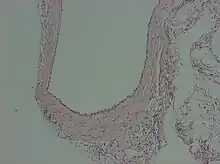

A peritoneal inclusion cyst is a cyst-like structure that appears in the pelvis due to non neoplastic reactive mesothelial proliferation, often as a consequence of prior episodes of pelvic inflammation, as can occur in pelvic inflammatory disease. It has the potential to mimic ovarian cysts, hydrosalpinx or even malignancy, due to its nonspecific anechoic appearance.[1]

Peritoneal inclusion cysts are commonly visualized on ultrasonography as a spider-web-like pattern. A normal-looking ovary is encircled by a big, irregular or oval, echolucent cyst with fine internal septations. The ovary is frequently located in the middle of the inclusion cyst or on its lateral aspect, appearing to be dangling inside the cyst.[2] Peritoneal inclusion cysts appear as a cystic mass with regular or irregular boundaries on CT scans, including material that has fluid or hemorrhagic attenuation properties. Cystic lesions with low T1 signal and high T2 signal, consistent with serous fluid, are shown on MR imaging.[7]